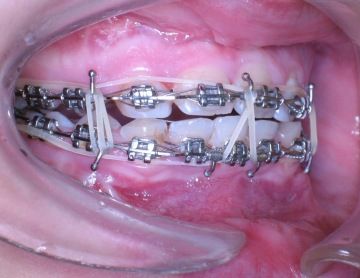

"Vaše dcera nemá kořeny zubů," zaznělo z úst zubního lékaře. Ano, opět čtete správně. Nemám kořeny zubů (můžete vidět na obrázku z RTG). A tím započala má zdlouhavá ortodontistická léčba fixním aparátem a ten mi v podstatě zůstal do dnes.

Během léčby se zjistil i zastavený růst čelistí (nemám všechny zuby), ten měl za následek i hluboký zkus zapříčiňující poškození čelistních kloubů. Bolesti a trnutí zubů je na denním pořádku.

Od té chvíle mi na zubech zůstaly fixační rovnátka, která drží všechny zuby při sobě se snahou udržet je v čelisti, co nejdéle to půjde a zabránit vypadnutí.